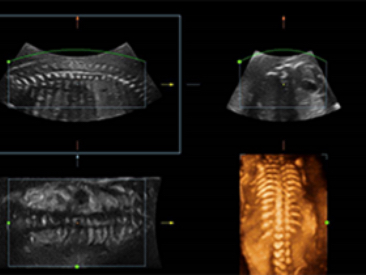

DE11-3E Dual-Volume Solution

DE11-3E Dual-Volume Solution

Images cliniques